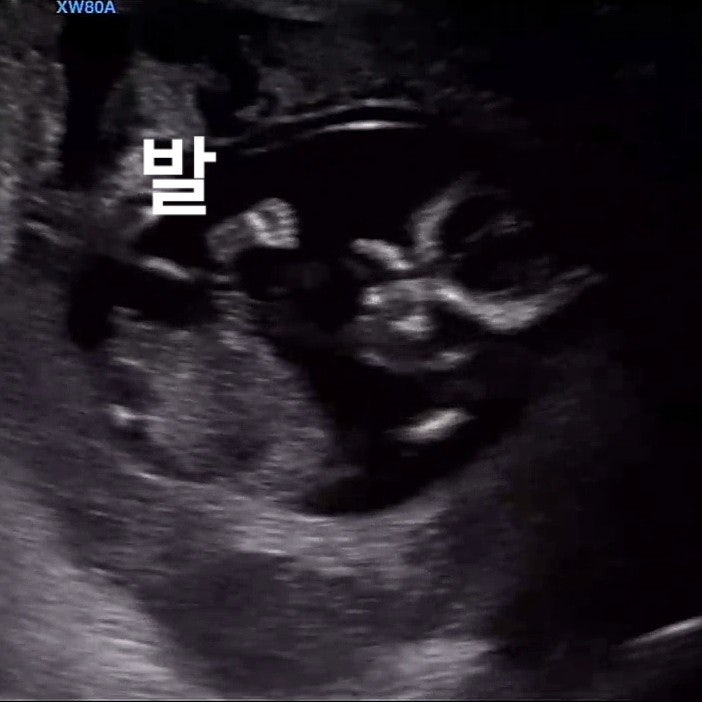

임신 11주 12주 13주 14주 15주16주 ㅣ 난임병원 라헬여성의원 졸업, 만35세 이상 임산부 1차 2차 기형아검사, 15주 태아 성별공개

임신 11주에서 16주까지 기록 2023.10.28~12.08 입덧 피크에서 신기하게 싹 가라앉은 후 찾아온 소화불량과...